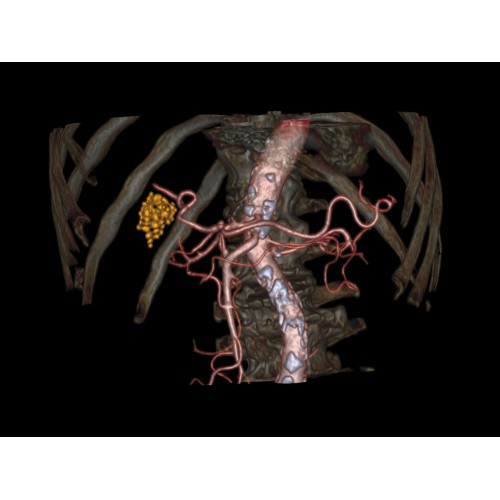

Позволяет проводить комплексные исследования всех анатомических зон, включая нейровизуализацию, ангиографию, исследования органов грудной и брюшной полости. Особенно эффективен для раннего выявления онкологических заболеваний.